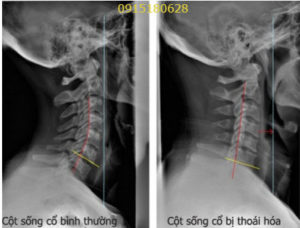

hình sảnh đót sống cổ

hình ảnh XQ